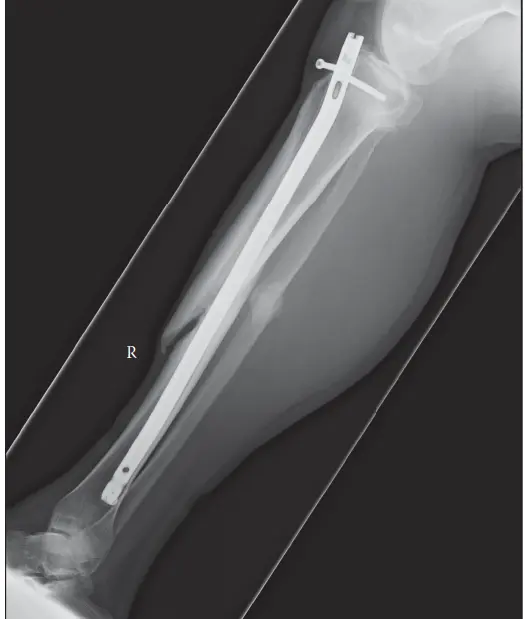

تؤثر كسور عدم الالتئام على ما يقرب من 5-10% من جميع الكسور، وتكون بعض المواقع التشريحية وفئات المرضى أكثر عرضة للإصابة بها. على سبيل المثال، تُظهر كسور عظم الساق (الظنبوب)، خاصة الكسور المفتوحة أو تلك التي تترافق مع إصابة شديدة في الأنسجة الرخوة، معدل عدم التئام يصل إلى 10-20%.

الشكل 1: مظهر إشعاعي لعدم التئام تضخمي نموذجي لعظم الساق، يتميز بتكوين كالوس وفير ولكن مع وجود فجوة واضحة في موقع الكسر، مما يشير إلى عدم استقرار ميكانيكي وليس نقصًا بيولوجيًا.

تؤكد "ميكانيكا بيولوجيا" التئام العظام على التفاعل الحاسم بين الاستقرار الميكانيكي والنشاط البيولوجي. تُصنف حالات عدم الالتئام بشكل عام بناءً على مظهرها الإشعاعي والفيزيولوجيا المرضية المفترضة:

- عدم الالتئام التضخمي (Hypertrophic Nonunion) : تتميز بتكوين كالوس وفير وواضح في صور الأشعة، ولكن دون حدوث ربط بين فجوة الكسر. يشير هذا الشكل إلى عملية بيولوجية نشطة تحاول الشفاء، ولكنها تفشل بسبب عدم كفاية الاستقرار الميكانيكي في موقع الكسر. يركز العلاج في المقام الأول على تعزيز الاستقرار والضغط.

- المسامير النخاعية (Intramedullary Nails) : توفر استقرارًا محوريًا ودورانيًا، ومشاركة في الحمل، وغالبًا ما تعزز إعادة التروية الدموية من خلال التجويف (Reaming). يُعد تبديل المسمار النخاعي لعدم التئام عظم الساق أو الفخذ فعالًا جدًا غالبًا بسبب تحسين الاستقرار والتحفيز البيولوجي من التجويف.